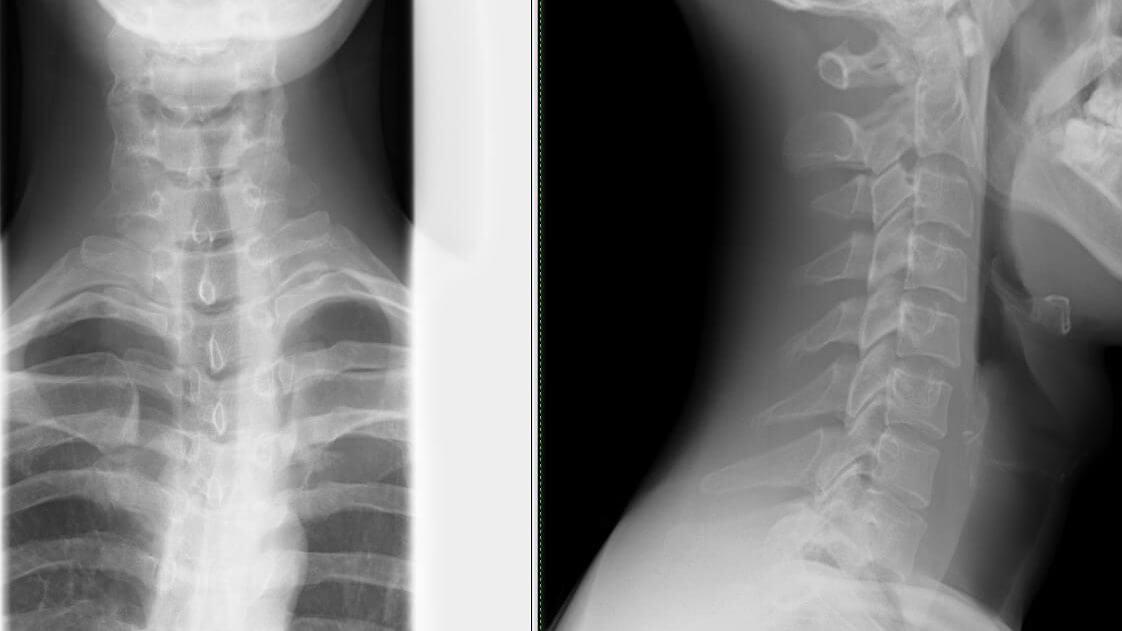

Сам механизм заболевания остеохондроза достаточно сложный. Деформация межпозвоночных дисков способствует уменьшению расстояния между позвонками, которые в свою очередь защемляют нерв. Именно это вызывает болевые синдромы. Остеохондроз шейного отдела считается самым опасным из существующих (грудной, поясничный), это связано с тем, что на шее проходит очень много артерий и нервных окончаний. Проявление данного недуга может привести к тому, что кислород не будет поступать в мозг, ухудшается кровообращение.

Первое, что стоит сделать, после проявления болевых ощущений – пройти диагностику врача, он расскажет вам про перерыты при остеохондрозе шейного отдела, о методах лечения и как избежать такого заболевания.